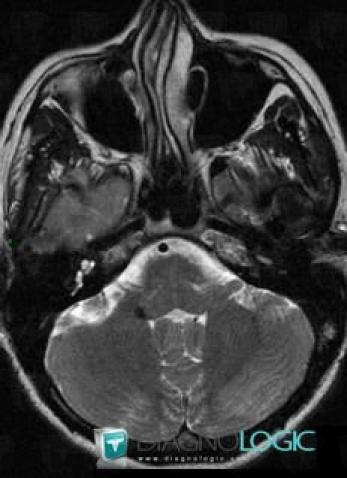

Cavernous angioma, Brainstem, MRI

Here is the specific information in the key image above:

- Diagnosis Cavernous angioma, Location(s) Brainstem, with gamuts